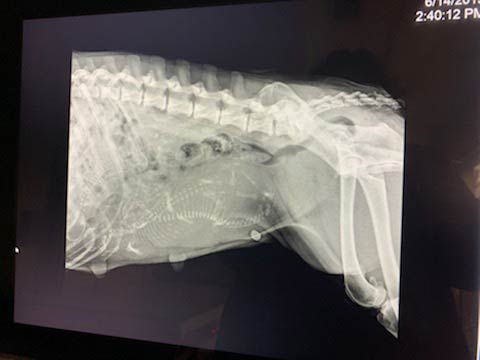

Diagnostic imaging can be an alternative to exploratory surgery. It allows us to examine your pet’s internal organs and body systems to better diagnose their conditions. There are different types of diagnostic imaging and the type your pet needs will depend on their symptoms and the affected area of the body.

With the shared goal of successful recovery, our team of experienced veterinarians works together to return your pet to good health. Our ultrasound and digital x-ray capabilities assist us in reaching our goal of recovery.

Pet Digital Radiology

Digital x-rays assist in diagnosing illness & injury.